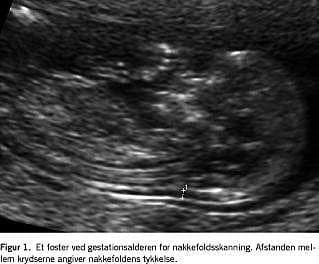

Nakkefoldsskanning

Ved nakkefoldsskanning måles den tynde væskeansamling, alle fostre har under huden i nakkeregionen (Figur 1 ). Det har vist sig, at jo tykkere denne væskebræmme er, desto større er risikoen for, at fosteret har Downs syndrom. Også andre kromosomanomalier og strukturelle misdannelser hos fosteret er associeret med en tyk nakkefold. Nakkefolden alene som screeningsmarkør har en DR på 70% ved en FPR på 5% [24]. Nakkefoldens tykkelse er ligesom serummarkørerne afhængig af fosterets GA, og angives derfor normalt i MoM.